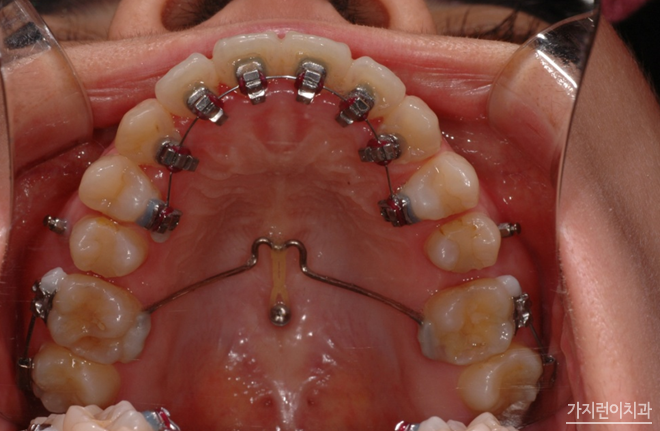

다음의 사진을 보면 미니스크류가 어떻게 이용되고 있는지 확인할 수 있는데요.

정말 작죠? 보시다시피 잇몸뼈나 입천장 등에 미니스크류를 심게 되는데요. 국소마취를 한 상태로 식립이 이루어지기 때문에 큰 통증은 없습니다. 하지만 마취가 풀리면 욱신거릴 수는 있어요. 꼭 필수는 아니지만 조금이라도 아픈 게 싫다?! 하는 분들이면 타이레놀 같은 진통제 복용이 도움이 됩니다. 또 나사를 뽑은 후에 잇몸에 구멍이 생기는 건 아니야? 하겠지만 공간이 작기 때문에 시간이 지나면 뼈와 살이 차오르게 됩니다. 걱정하지 않아도 된다는 소리죠-